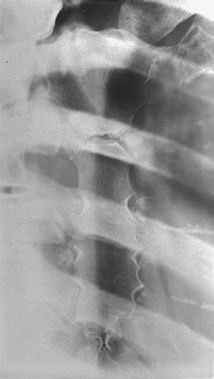

What does under-rotation look like in RAO sternum?

Sternum still superimposes spine.